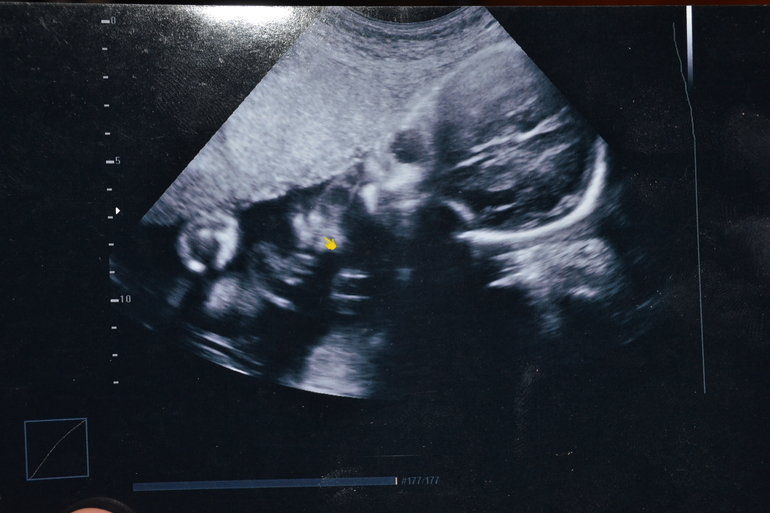

20 неделя

Вроде 2 однотипные фотки, но я всматриваюсь в каждый миллиметр и вижу разницу, на первой щечки надутые и как буд-то палец во рту, а на второй втянутые